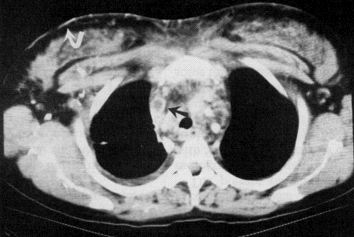

Dəqiqləşdirmə

Kəskin mediastinitin diaqnozunu dəqiqləşdimək üçün ən vacib müayinə KT-dir. KT-də divararalığında ödem, maye, hava, kontrast ekstravazasiyası mediastinitin xarakterik əlamətləridir.

• KT-də divararalığında ödem, maye, hava, bəzən də kontrast ekstravazasiyası (Şəkil 10)